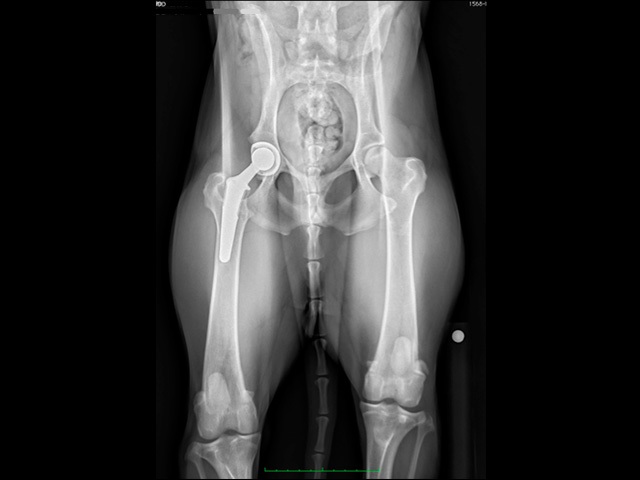

股関節形成不全Hip Displasia ゴールデンレトリーバー2歳オス CFX L:手術直後 R:8年 バーニーズマウンテンドッグ14ヶ月齢 BFX 手術3ヶ月後 イヌの股関節形成不全は、股関節の緩みや関節炎の原因となる遺伝的疾患です。正常な股関節は、骨盤側の寛骨臼と大腿骨側の大腿骨頭とがしっかりと連結した球状関節を形成しますが、股関節形成不全の場合ではこの連結は次第に緩み、部分的変位または亜脱臼を示すようになります。亜脱臼は、後に関節炎や形成異常の原因となります。 イヌ股関節形成不全症の発生には未だに不明な点が多く、遺伝、過剰栄養、エストロゲンの代謝不均衡、運動性の向上などの環境因子が影響しているといわれている。また、動物の急速な成長は股関節コンポーネントの不均衡をもたらし、運動性の増加は未熟な関節に対して過剰なストレスを加え続ける結果となります。 股関節形成不全の治療は、症状や関節変性の強弱により異なります。X線検査で構造異常が偶然見つかった場合でも、明らかな症状が見られない場合には治療の対象にはなりません。症状が軽度の場合には、犬用の非ステロオイド性抗炎症剤(NSAIDs)の投与が有効な場合があります。成長期にあって関節の緩みがあり、かつ変性が見られない場合には、寛骨臼の被覆角度を大きくする骨盤三点/ニ点骨切り術(TPO/DPO)が適応となり、それ以外では股関節全置換術(THR)が最良の治療方法となります。痛みを解消する目的で大腿骨頭を切除する大腿骨頭骨頚切除術(FHO)は、特に大型犬では荷重関節の消失による跛行をもたらすため、非常時の救済的手術法として位置付けられています。 椎間板ヘルニア/その他 股関節脱臼